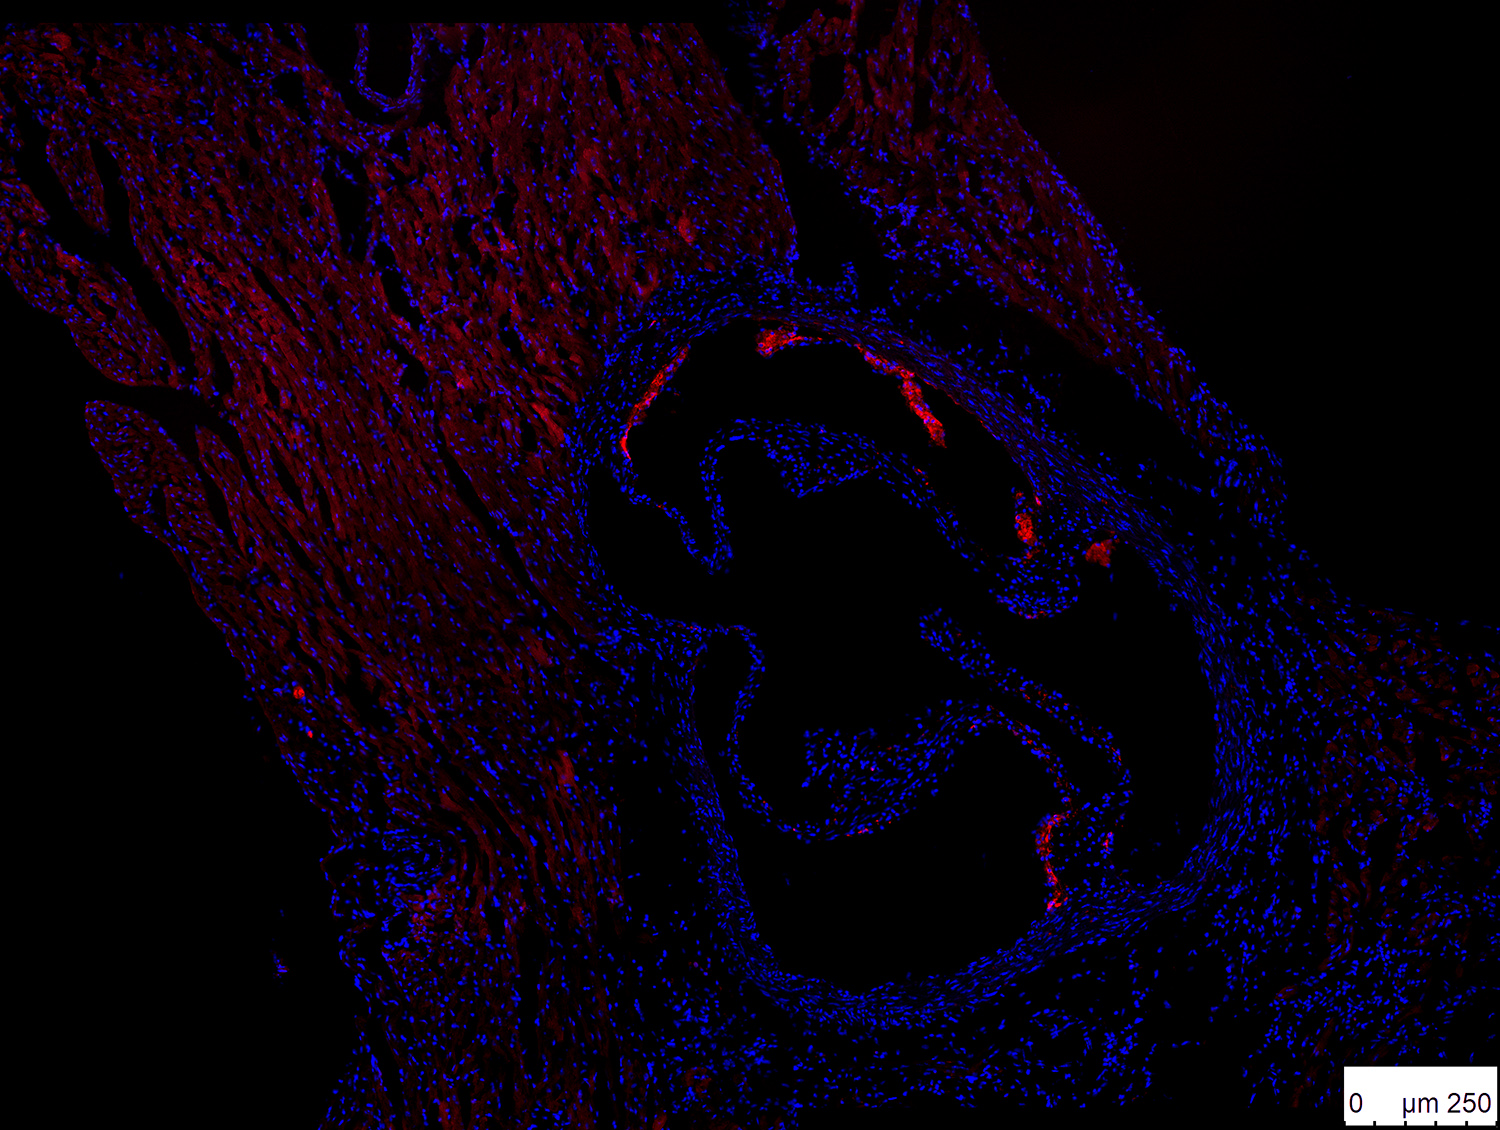

(Wien, der 12. Juni 2018) Atherosklerose, die krankhafte Verengung von Blutgefäßen, ist die Hauptursache für Herzinfarkte und Schlaganfälle, welche von der WHO nach wie vor als die weltweit häufigsten Todesursachen geführt werden. In der Entwicklung von Atherosklerose spielen weiße Blutkörperchen, die sogenannten B2-Lymphozyten, eine entscheidende Rolle. Sie benötigen ein Molekül, das Forschenden unter dem Akronym BAFF bekannt ist. Da ein Ausschalten des BAFF-Rezeptors auf der Oberfläche der B2-Lymphozyten der Entwicklung von Atherosklerose in Maus-Experimenten entgegenwirkt, lag die Vermutung nahe, dass ein ähnlicher Effekt eintritt, wenn BAFF direkt angegriffen wird.

Mit speziellen Antikörpern, die sich zielsicher an BAFF binden, kann das Molekül unschädlich gemacht werden. Diese Antikörper haben WissenschaftlerInnen des CeMM Forschungszentrum für Molekulare Medizin der Österreichischen Akademie der Wissenschaften und der Medizinischen Universität Wien in Zusammenarbeit mit der University of Cambridge auf ihre Wirkung in der Entstehung von Atherosklerose in Mäusen getestet – mit überraschendem Ergebnis: Anstatt wie erwartet die Bildung der gefürchteten „Plaques“ in den Arterienwänden der Mäuse zu reduzieren, wurden diese Einlagerungen größer. Die Studie wurde in der Fachzeitschrift Circulation veröffentlicht. (DOI: 10.1161/CIRCULATIONAHA.117.032790)

„Wir konnten eindeutig zeigen, dass die B2-Lymphozyten durch die Anti-BAFF-Antikörper nicht mehr überleben konnten und effizient eliminiert wurden“, beschreibt Letztautor Christoph Binder, Gruppenleiter am CeMM und Professor für Atheroskleroseforschung an der MedUni Wien, die Ergebnisse der Studie. „Zu unserer Überraschung haben sich jedoch die Plaques dadurch sogar vergrößert, was auf eine bisher völlig unbekannte Rolle des BAFF-Moleküls hindeutete. In weiteren Experimenten gelang es uns dann, dieses Phänomen zu erklären“.

Die ForscherInnen fanden heraus, dass BAFF auch eine entzündungshemmende Wirkung hat, die sich positiv auf die Plaque-Bildung und das Atherosklerose-Risiko auswirkt. Bei diesem Mechanismus bindet BAFF an einen alternativen Rezeptor (TACI) auf anderen Immunzellen. Und es konnte gezeigt werden, dass BAFF in diesen Zellen einen entzündungshemmenden Prozess in Gang setzt. Dieses Ergebnis könnte bedeutende Implikationen für die Atheroskleroseforschung und -vorbeugung haben: Es gibt zum Beispiel Menschen mit Mutationen in dem Gen für TACI und diese könnten ein erhöhtes Risiko für Atherosklerose und in Folge Herz-Kreislauf-Erkrankungen aufweisen.